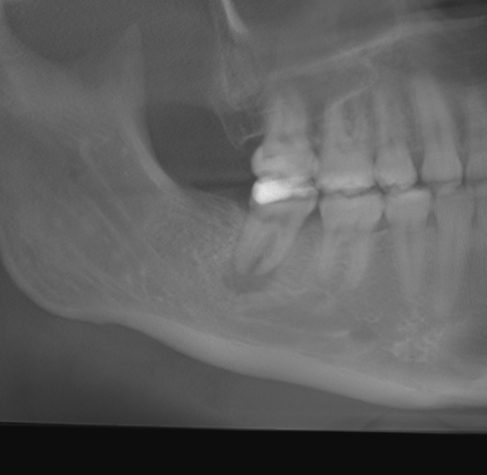

In the GIF above, you can see I received a 3D panoramic X-ray. The process took about 10 seconds and it’s about the same exposure to X-rays as a flight from San Francisco to Los Angeles, Dr. Aamodt said.

“With that information, we’re able to see the health of your roots, your teeth, the bone, your jaw joints, check for anything that could get worse during treatment,” Dr. Aamodt said.

Below, you can see the 3D scan.

Next is looking in-between the teeth. From here, the idea is to get a much more holistic view, Dr. Aamodt said. This is where things got interesting.

If you look at the bottom left of the photo, under my back bottom tooth, you can see a dark circle below the tooth. Dr. Aamodt gently pointed that out to me.

“That tells me there’s bacteria living inside of your jaw,” he explained. “A lot of people have this. It’s pretty common so don’t beat yourself up for it.”

This is when he told me I’d likely need to get a root canal to get rid of it. Mild panic ensued.

Dr. Aamodt went on to explain that, if I were a patient of his looking to get my teeth straightened, he would recommend that I first get the root canal before any teeth movement. That’s because, he explained, moving teeth at that point could potentially result in further infection.

“The concern about that is when we move a tooth with that, the infection will get worse and you could risk losing that tooth,” he told me.